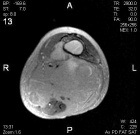

A.M. - 87 year old female with an asymptomatic posterior thigh soft tissue mass present for many years, the patient reports that it has increased in size over the past three months